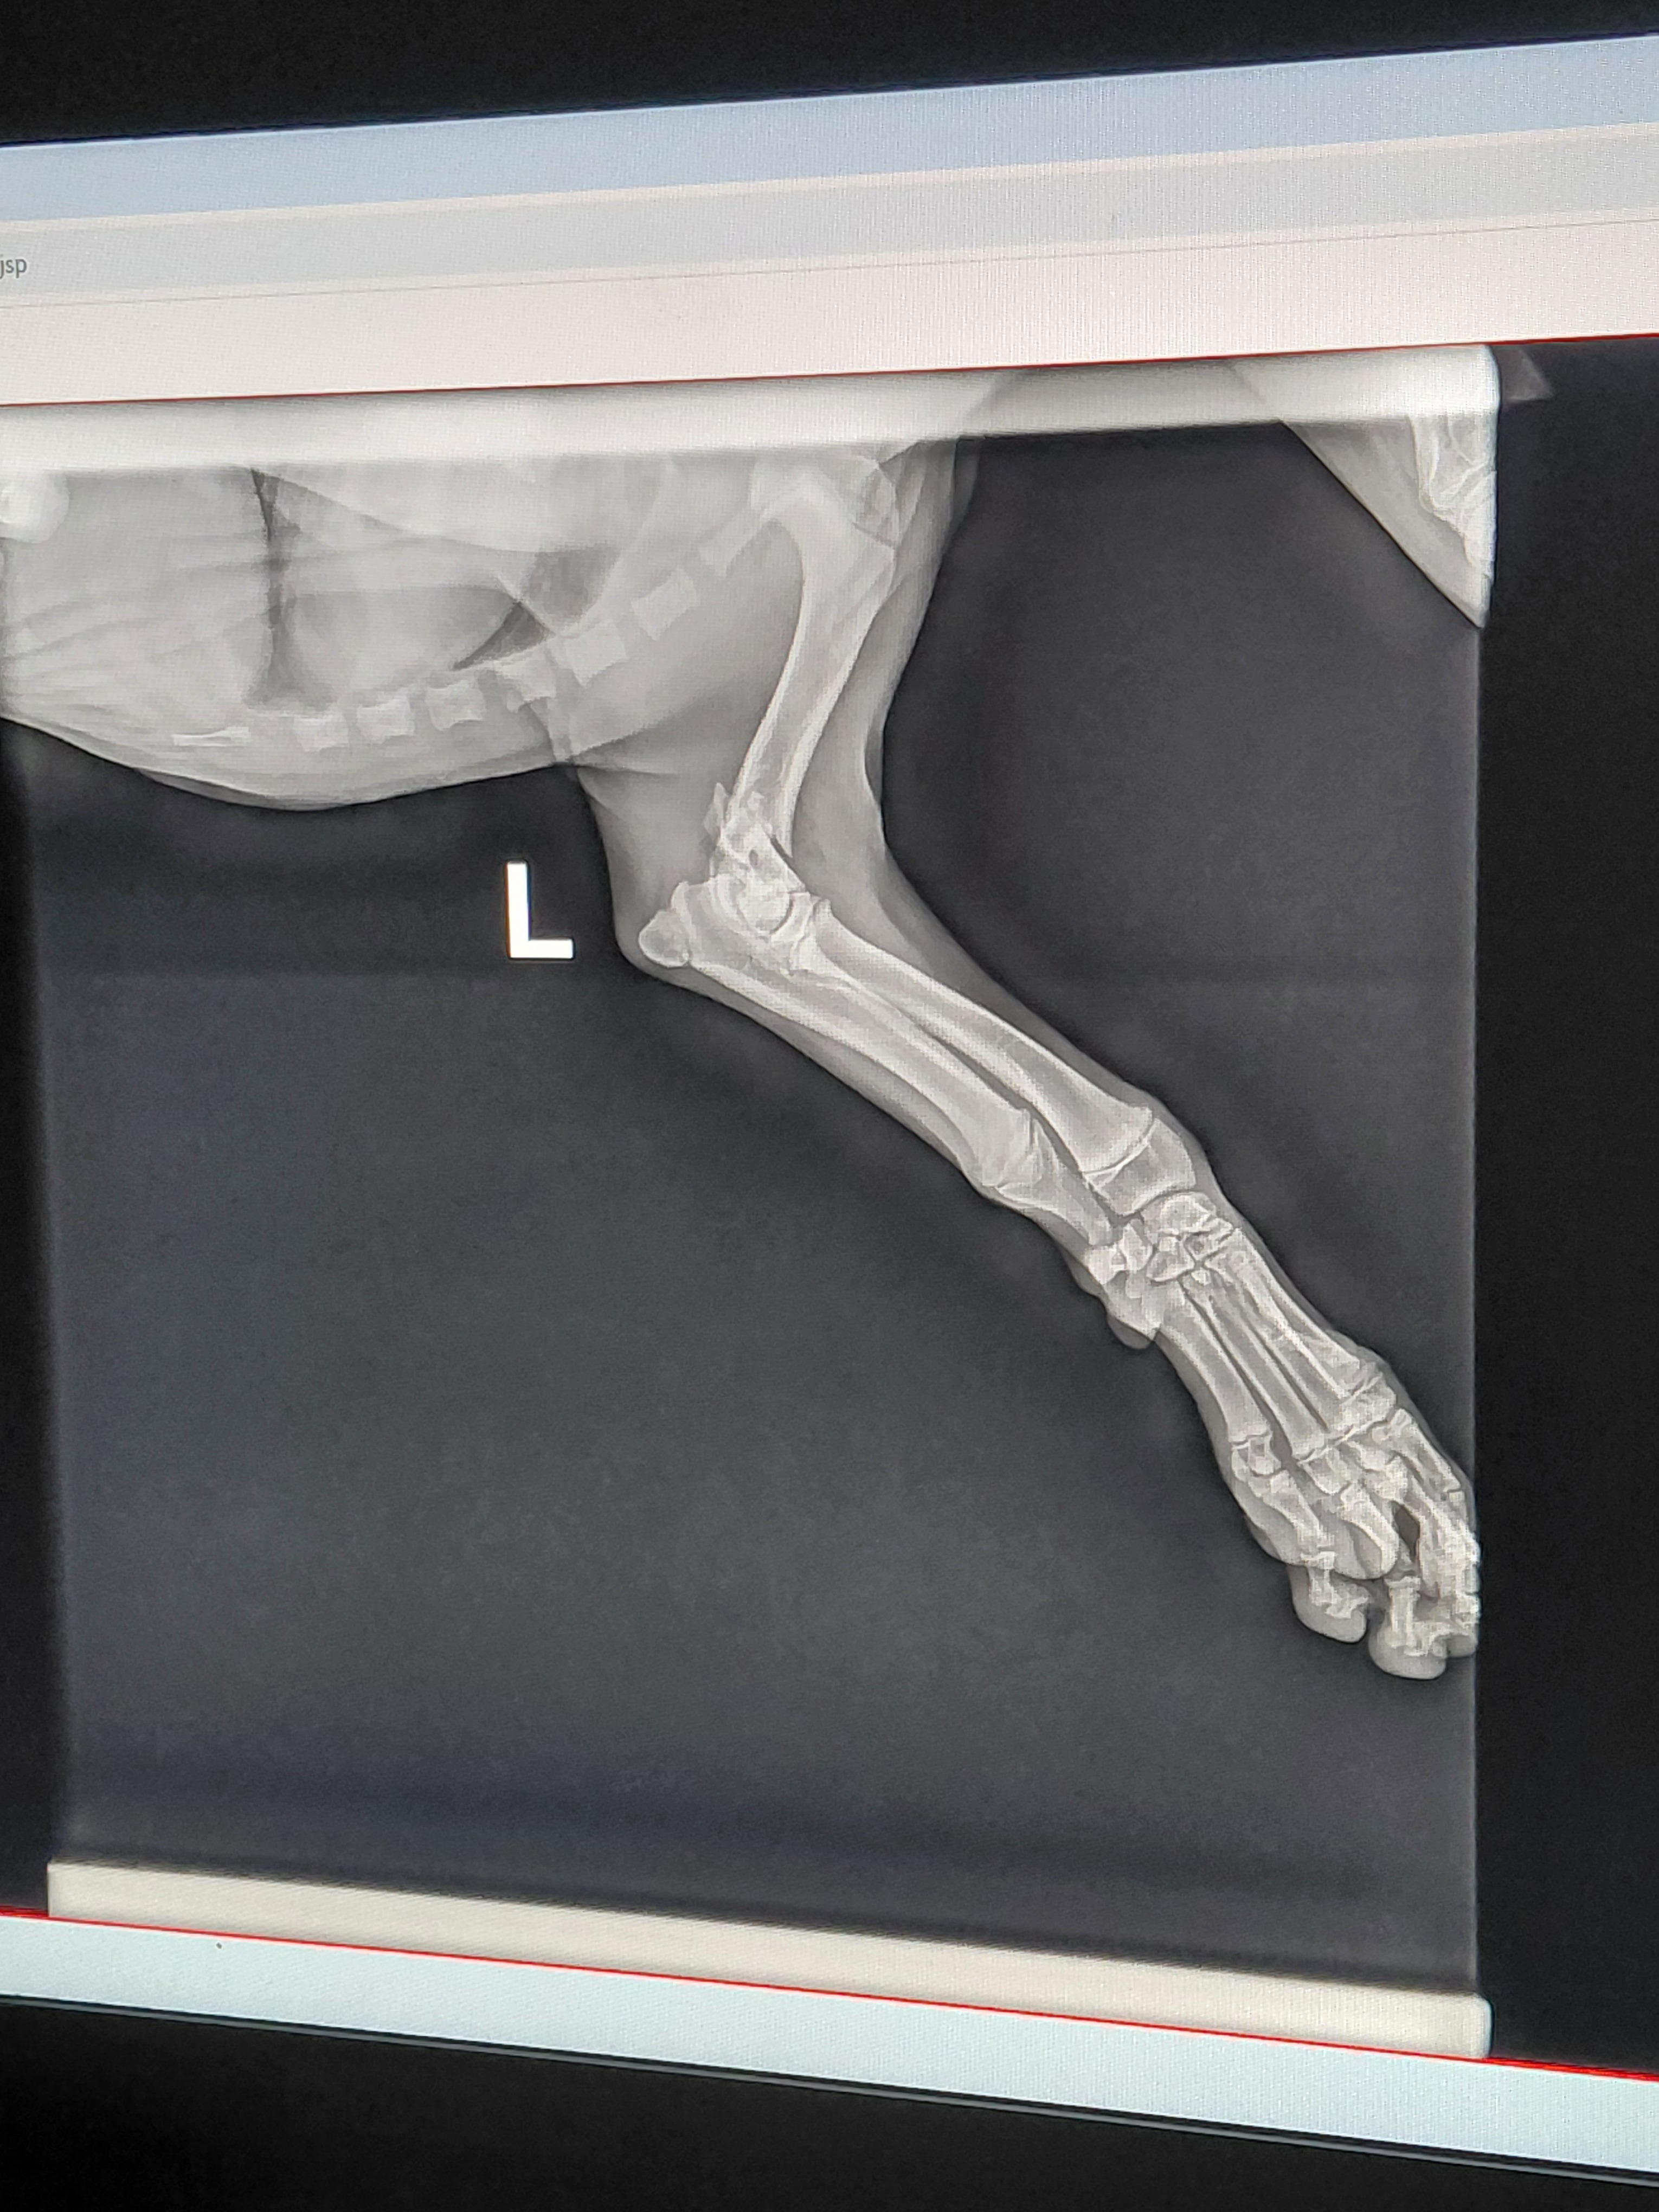

This fundraiser is for our 4 month old puppy Blue who injured his leg while playing outside.he fell and has a TY fracture.and it will need to be Amputated. . Amputation surgery and after care is more costly then we can afford. Any help would be very appreciated. Without the surgery the leg will not heal right and he will develop arthritis in the joint he will be in a lot of pain.